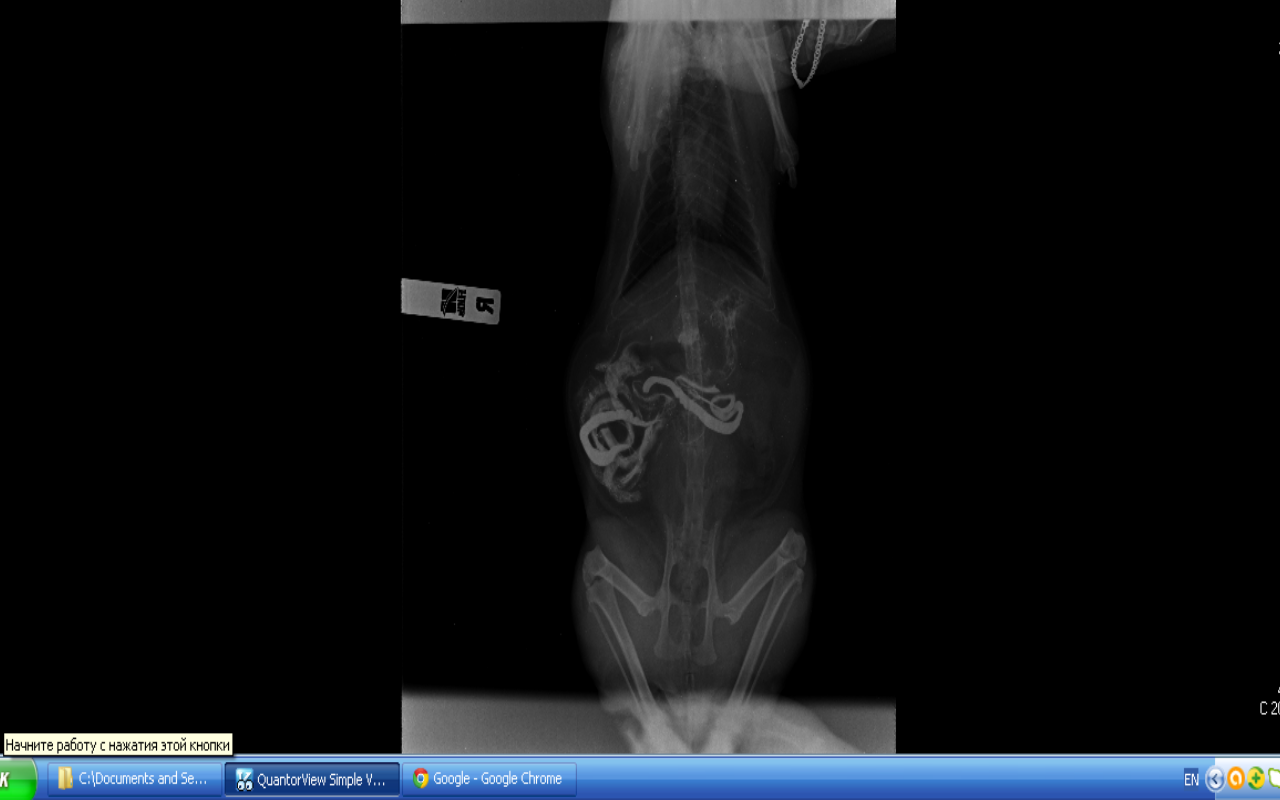

Рентген:

Вложения

1.jpg

2.png

рыжка 1.png

рыжка 2.png

Самое главное, после позавчерашнего рентгена с контрастом она не ходила по-большому. Где -то у нее этот сульфат бария сидит, меня это очень настораживает, когда делали рентген, врач сказала, что до толстого кишечника контраст еще не дошел, может у нас в нем проблемы?

4 часа просидели в очереди!!! Были на приеме у 8-го по счету врача, сделали еще раз рентген. Врач сказал:

1. В толстом кишечнике вроде тоже все нормально.

2. Что не было стула - там все на подходе, контрастное вещество может вызвать запор, это обычное, в случае правильной работы кишечника, явление.

3. Очень долго рассматривал все наши 3 снимка и однозначно сказал, что на всех снимках в каловых массах очень много шерсти (Рыжка на самом деле очень чистоплотная кошка, постоянно вылизывается). Эта невыходящая шерсть может прилипать к стенкам желудка и кишечника и образовывать воспаления и язвочки.